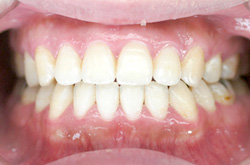

上あご・正面・下あご

before

after